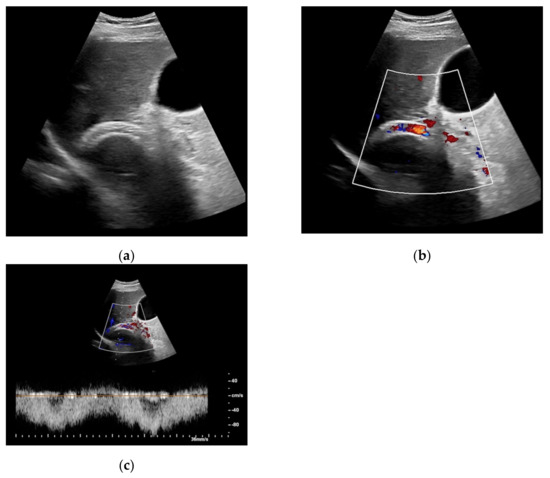

Figure 5. Same patient as in Figure 2. After administration of intravenous contrast, no intraluminal microbubbles can be registered within the transjugular intrahepatic portosystemic shunt compatible with complete occlusion (a,b).